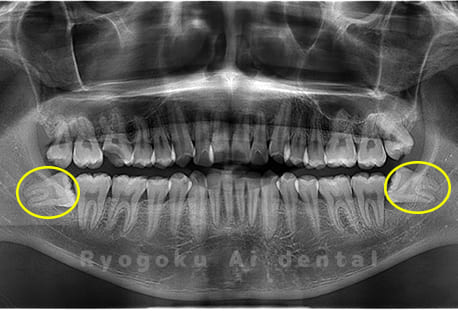

Case04

-

- 原因

- 上顎の親知らず、下顎の水平埋伏の親知らず

- 治療内容

- 上顎の親知らず、下顎の水平埋伏の親知らずを抜歯したケースです。

<リスク・副作用>

手術後は痛み、腫れ、痺れなどの副作用が生じる場合があります。